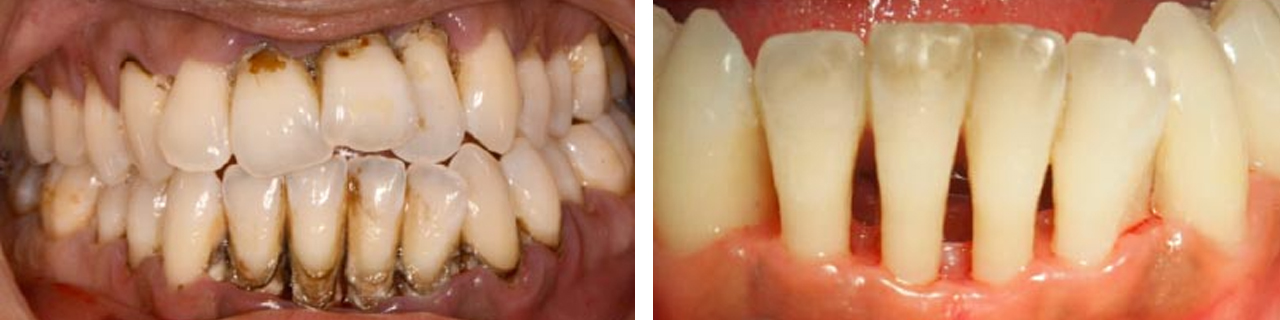

Eliminación de cálculo mediante raspado y alisado radicular.